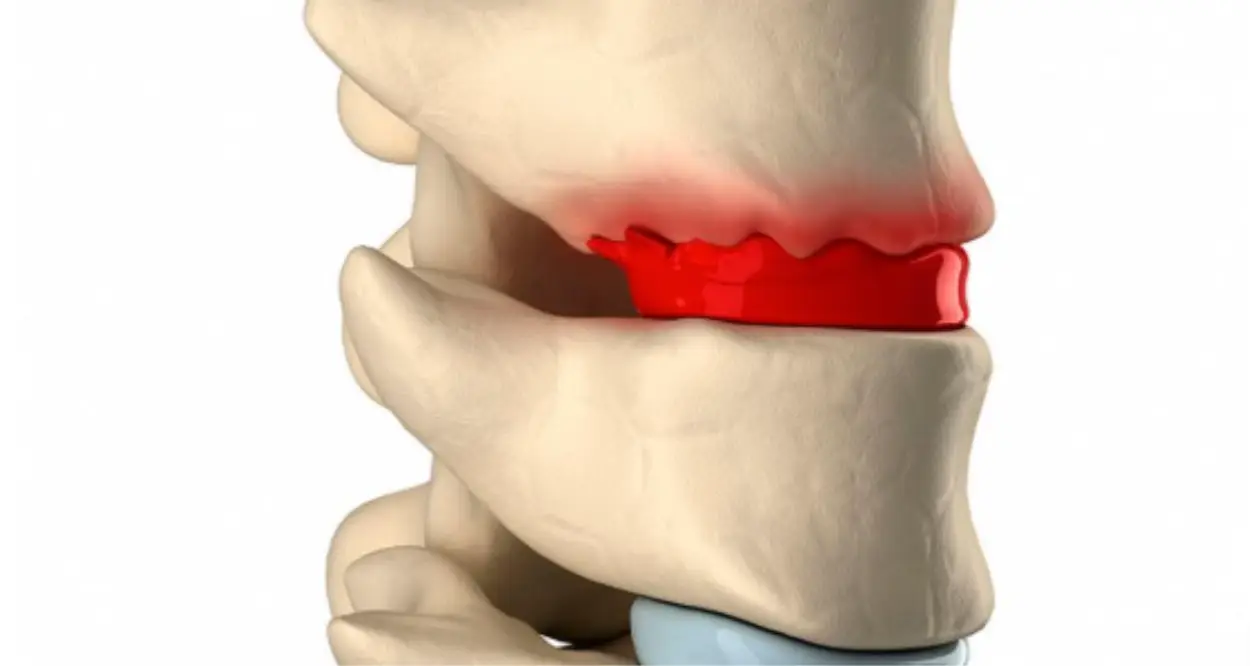

Hernia de Disco: Qué es y Cómo Afecta Tu Salud

## ¿Qué es una hernia de disco?La columna vertebral está formada por vértebras apiladas, separ...

Enfermedad del Disco Intervertebral: Causas, Síntomas y Soluciones

La enfermedad del disco intervertebral es una condición frecuente que afecta la columna vertebral, ...